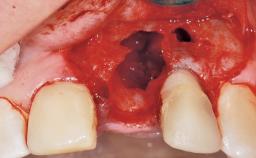

Immediate Flapless Placement of an Implant in a Maxillary Right Lateral Incisor Site

This 43-year-old male patient, a non-smoker, came to our practice because of a fracture of tooth 12 caused by a bicycle accident. Due to the combined para- and infrabony crown and root fracture, tooth extraction, and subsequent implant placement were suggested to the patient as the therapy of choice. The patient had high esthetic expectations with regard to the treatment outcome and asked for an immediate fixed provisional restoration. His individual esthetic risk profile summed up to a medium esthetic risk.

Placement Protocol Immediate implant placement

Socket Morphology Single-root socket

Socket Integrity Sufficient, with intact bone walls

Bone Volume Sufficient, with intact walls